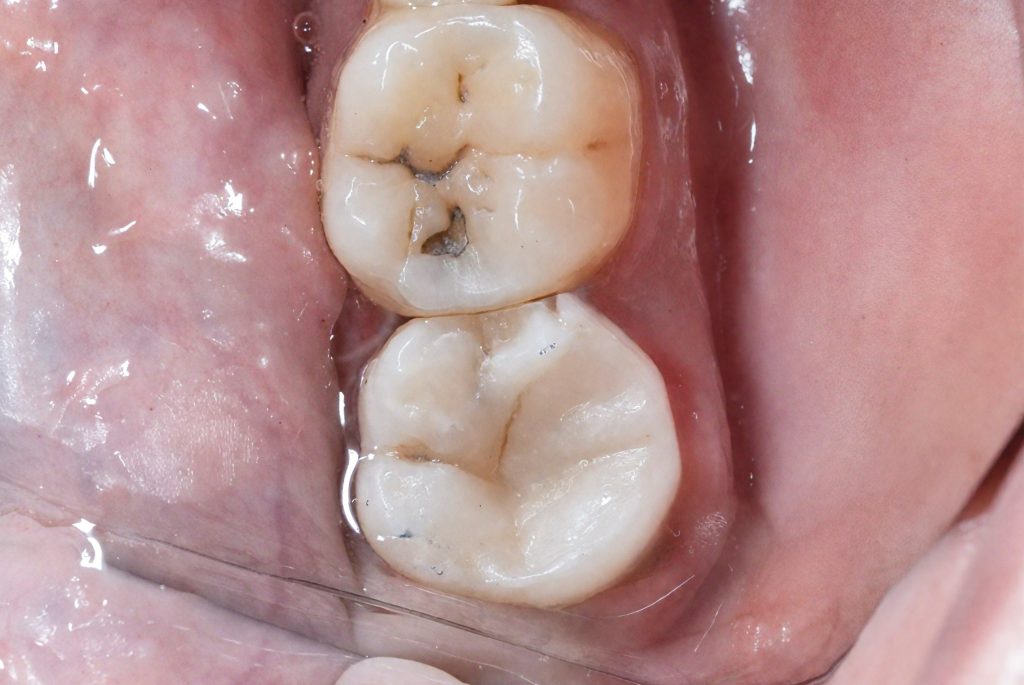

5 Adhesive Reconstruction and Cuspal Coverage

Selective enamel etching with 37 % phosphoric acid was followed by application of 8th-gen adhesive (BISCO).

Incremental anatomic layering was done with Tokuyama Estelite Sigma Quick, building primary and secondary anatomy under scope.

Cuspal coverage was performed biomimetically, ensuring ideal occlusal contact and stress distribution (Fig 8 & 9).

7️⃣ Anatomic layering with Tokuyama Estelite

8️⃣ Occlusal final view – cuspal coverage